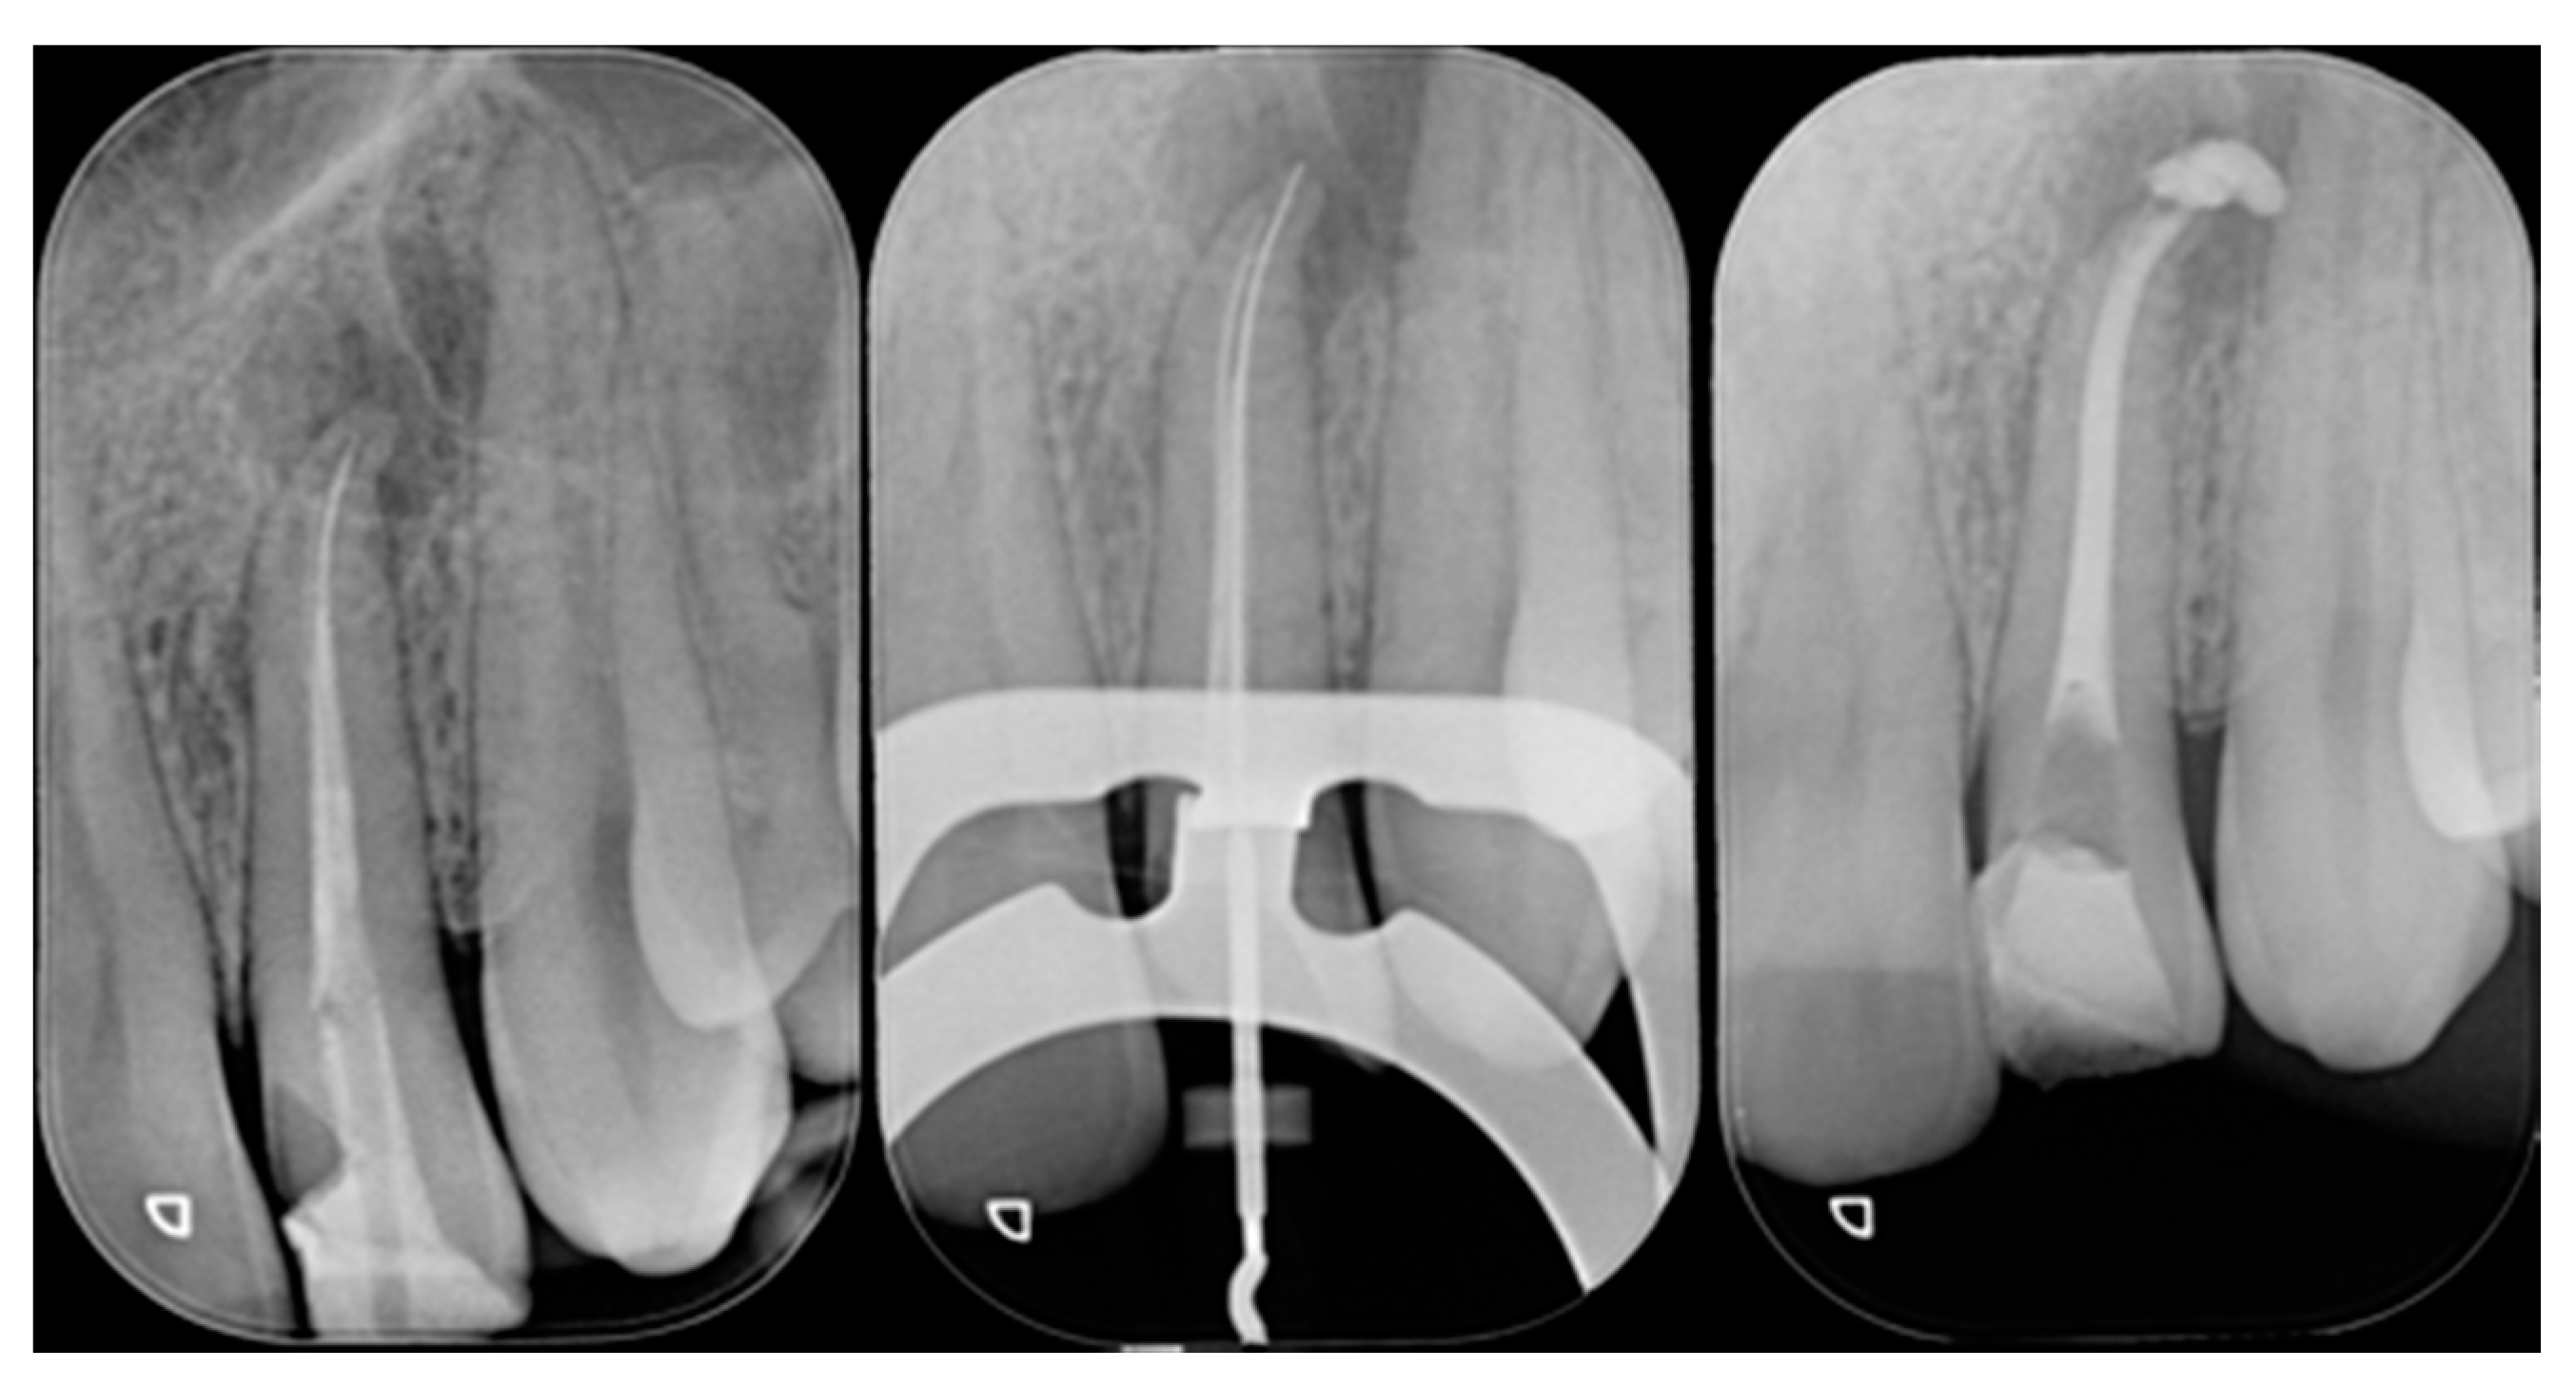

A 42-year old woman presented to the clinic with esthetic concerns related to her upper left lateral incisor (Figure 20). Pre-operative x-rays showed periapical lesion that required retreatment. After retreatment (Figure 21) a treatment plan was proposed to the patient. The ideal treatment would have involved an orthodontic therapy to gain back lost space in mesial portion. The patient decided not to consider an orthodontic treatment and accepted just the restorative proposal (Class IV restoration). Considered the sufficient amount of ferrule no post was applied [16]. Shade was selected as described in previous case, using the button-try technique [14]. After isolation with rubber dam, preparation (Figure 22) and adhesion (Clearfil SE, Kuraray Noritake Dental, Tokyo, Japan), composite frame was completed (Clearfil Majesty ES-2, A1D, Kuraray Noritake Dental, Tokyo, Japan) with silicone index and interproximal transparent mylar matrices (Figure 23). Interproximal walls were considered too thick; therefore, they were reduced (Figure 24) using diamond bur as described in Section 2.1.2. This allowed the internal dentinal body to have the correct volume (Figure 25) and therefore to respect ideal opacity/translucency ratios. Restoration was therefore completed adding enamel layer (Clearfil Majesty ES-2, A1E, Kuraray Noritake Dental, Tokyo, Japan) and performing finishing and polishing procedures (Figure 26 and Figure 27) as described in previous clinical case. The restoration shows good integration 6 months post-operative (Figure 28 and Figure 29).

Figure 21.

Initial x-ray, during and after endodontic retreatment. Reprinted from Restauri diretti nei settori anteriori, G. Paolone, S. Scolavino, © 2021, with permission from Quintessence Publishing Italy.